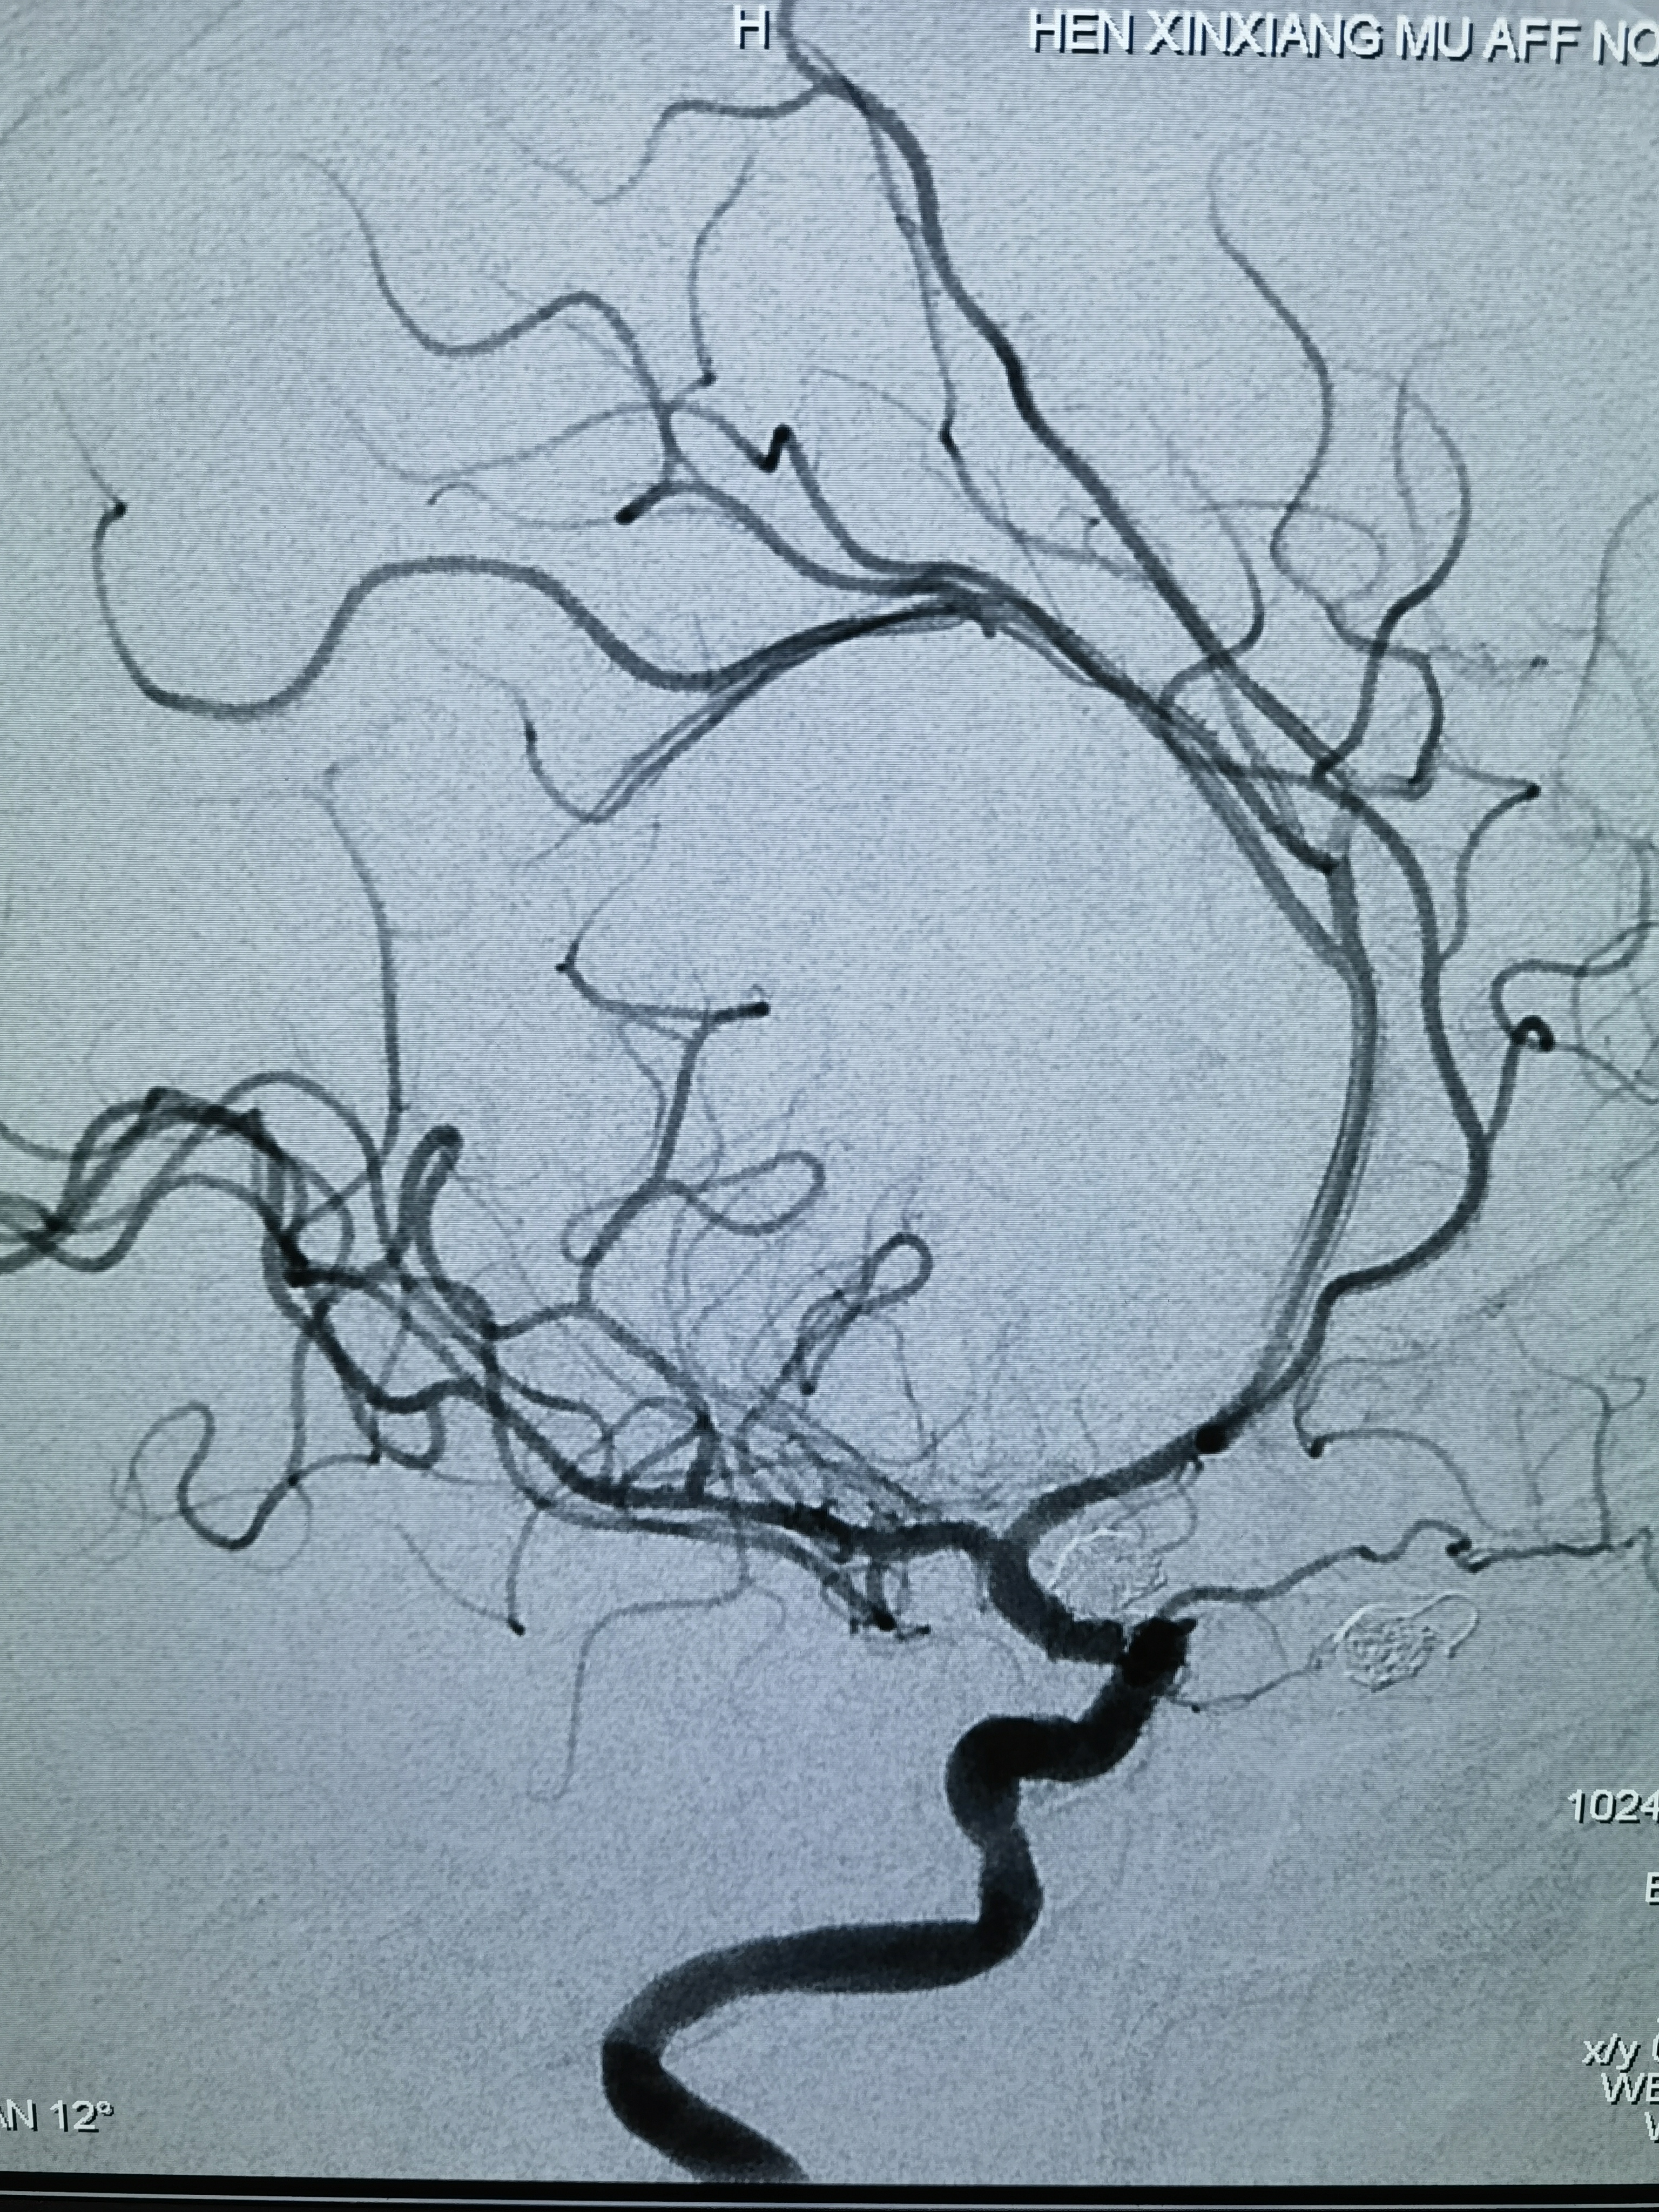

三维旋转造影

第三次出血后急诊上台,造影显示动脉瘤增大

工作位造影,瘤体约6.1*5.5mm,更加确认是血泡样动脉瘤!